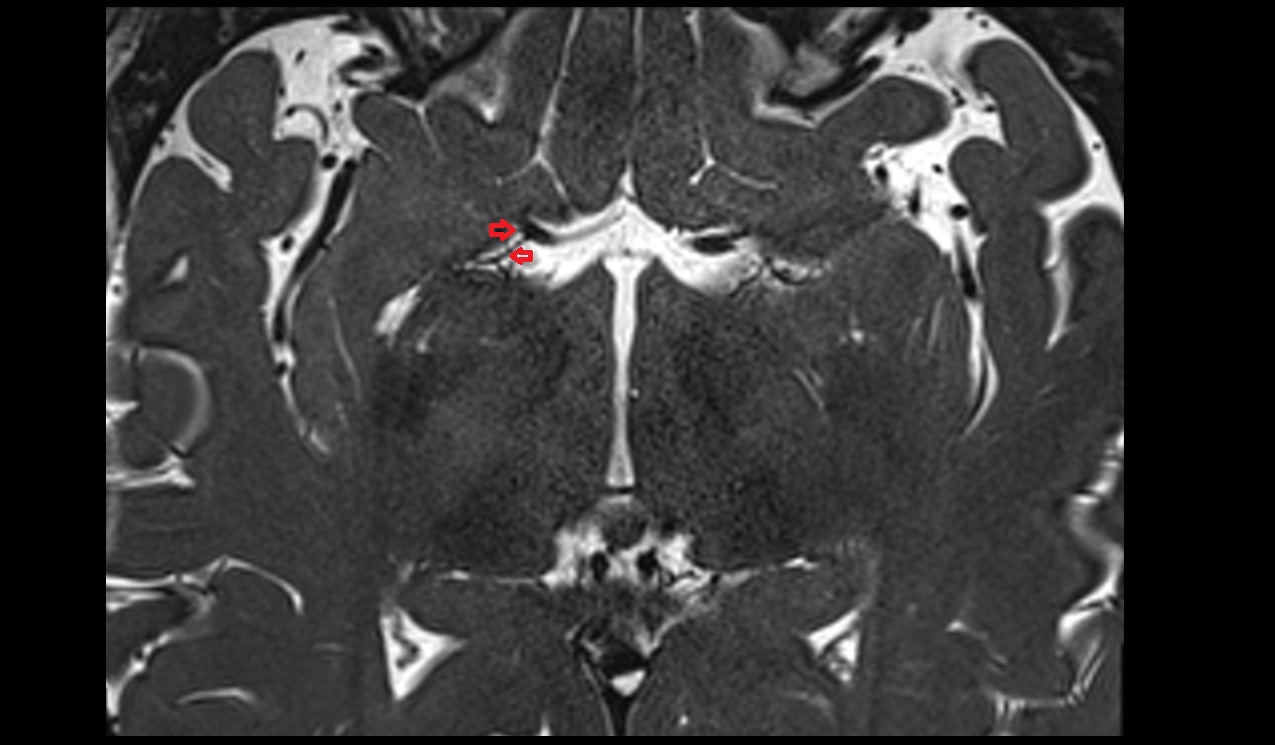

- Hippocampus